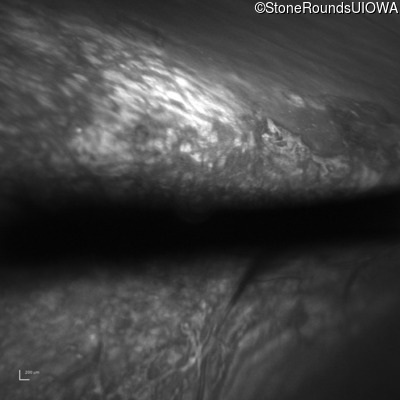

Optical Coherence Tomography - Right - 20/200 sc

Exemplar / OCT Stack